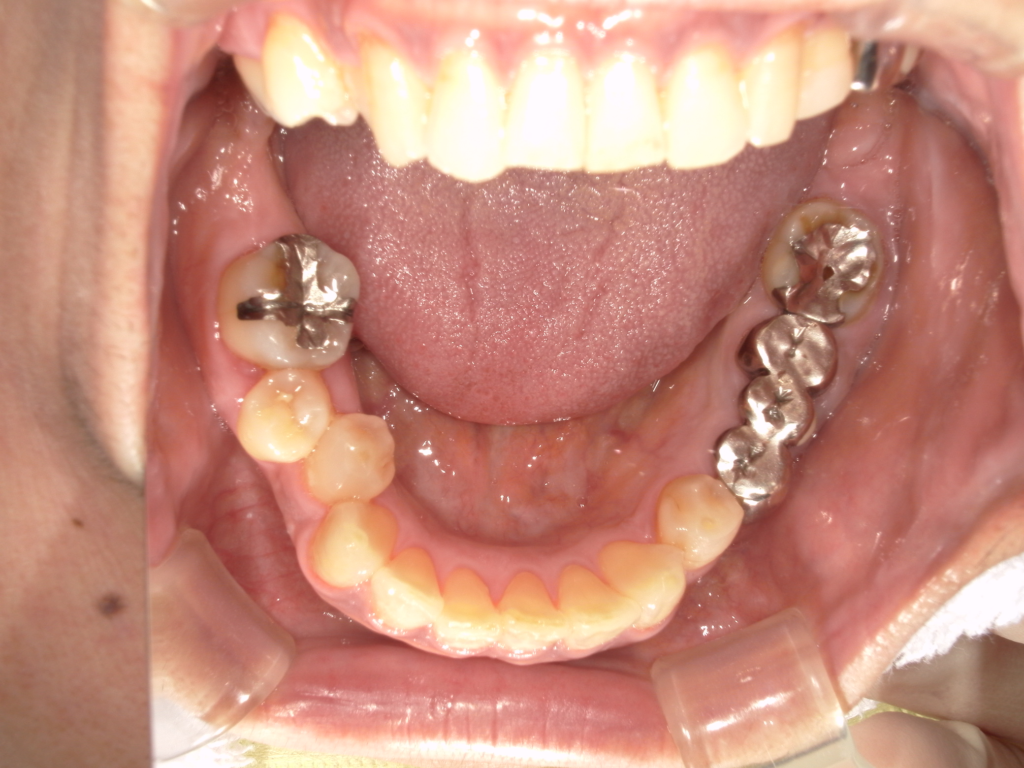

Y様インプラント実例 #44

左の上下の奥歯をインプラントで治療しています。

左下の奥歯は歯を抜くのと同時にインプラントの埋め込みを行っています。

被せものは上下、セラミックスで作っています。

治療前

治療後